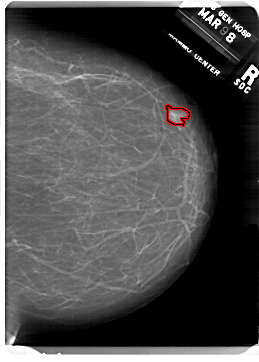

FILE: A_1815_1.RIGHT_CC.OVERLAY

TOTAL_ABNORMALITIES 1

ABNORMALITY 1

LESION_TYPE MASS SHAPE TUBULAR MARGINS CIRCUMSCRIBED

ASSESSMENT 4

SUBTLETY 4

PATHOLOGY BENIGN

TOTAL_OUTLINES 1

BOUNDARY